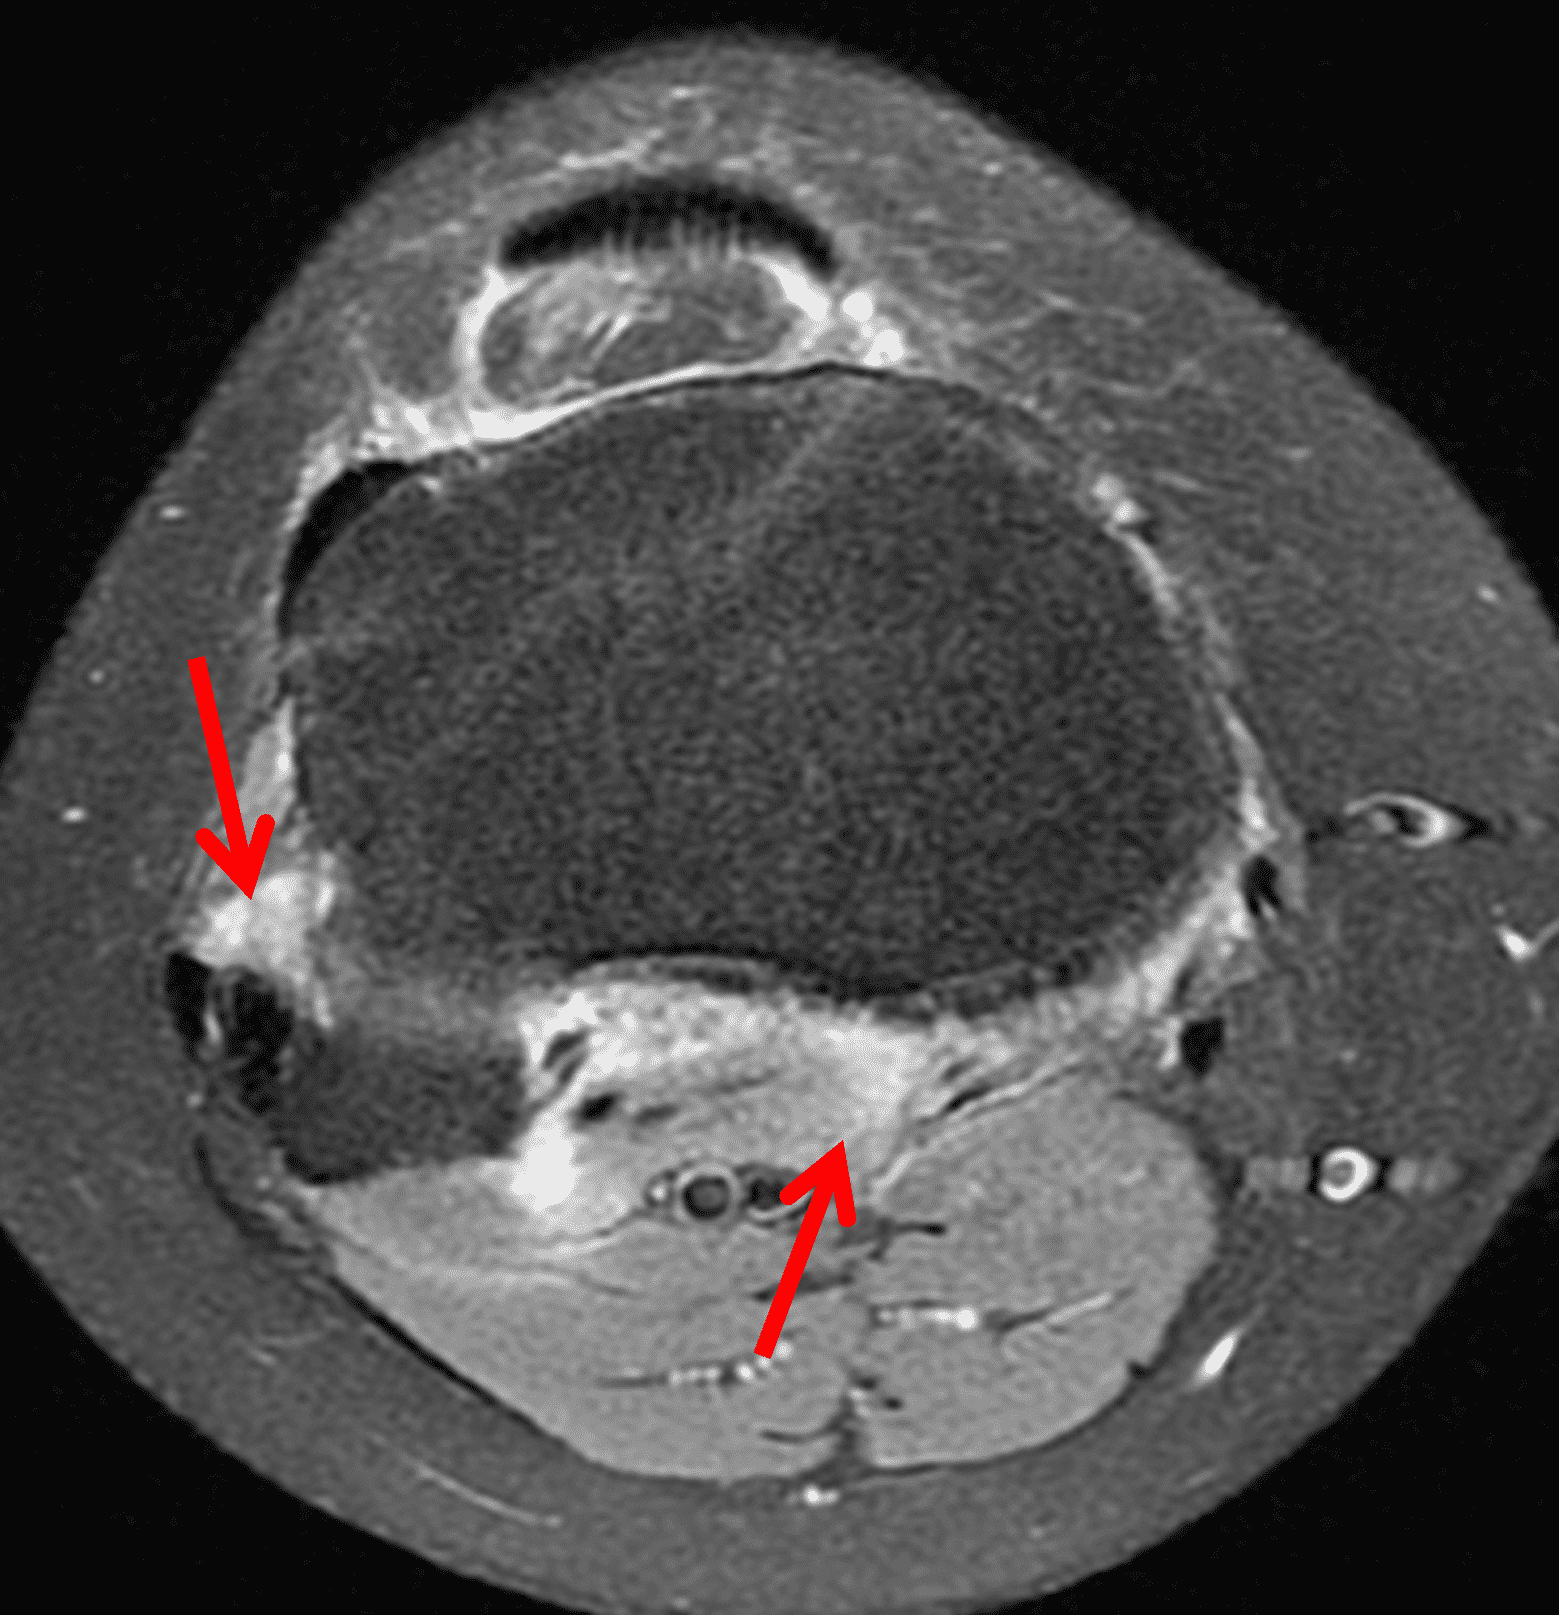

Figure 2: (2A) The coronal image shows a large effusion and severe hypertrophic synovitis (asterisks) in the knee. (2B) On the sagittal image the hypertrophic synovium (asterisks) involves the suprapatellar and infrapatellar recesses as well as the anterior and posterior intercondylar notch. A reactive lymph node (arrow) is present in the popliteal fossa. (2C) The axial image demonstrates myositis (arrows) involving the popliteus and peroneus longus muscles. Note the preserved articular cartilage, lack of erosions, and the absence of subcutaneous or marrow edema.

The causative spirochete invades the synovium, triggering a host inflammatory response that leads to synovial hypertrophy and inflammation, resulting in the characteristic clinical symptoms and imaging findings associated with Lyme arthritis.2 Common MR findings associated with Lyme arthritis include synovitis, joint effusion, popliteal lymphadenopathy, and myositis predominantly involving the popliteus (Figure 4).2,3,9 In contrast to acute septic arthritis due to more common bacteria, subcutaneous edema, marrow edema, erosions, and osteomyelitis are uncommon (Figure 4C).

Figure 4: Lyme arthritis. Fat-suppressed, fluid-sensitive images. (4A) Transverse image shows severe proliferative synovitis in the anterior and posterior joint recesses (arrows). Note the lack of surrounding subcutaneous edema. (4B) In addition to synovitis, the sagittal image shows multiple reactive lymph nodes (red arrows) and popliteal myositis (white arrow). (4C) Coronal image also shows patchy non-joint centered marrow edema in the distal femur and proximal tibia (asterisks), which is uncommon in Lyme disease compared to acute septic arthritis.